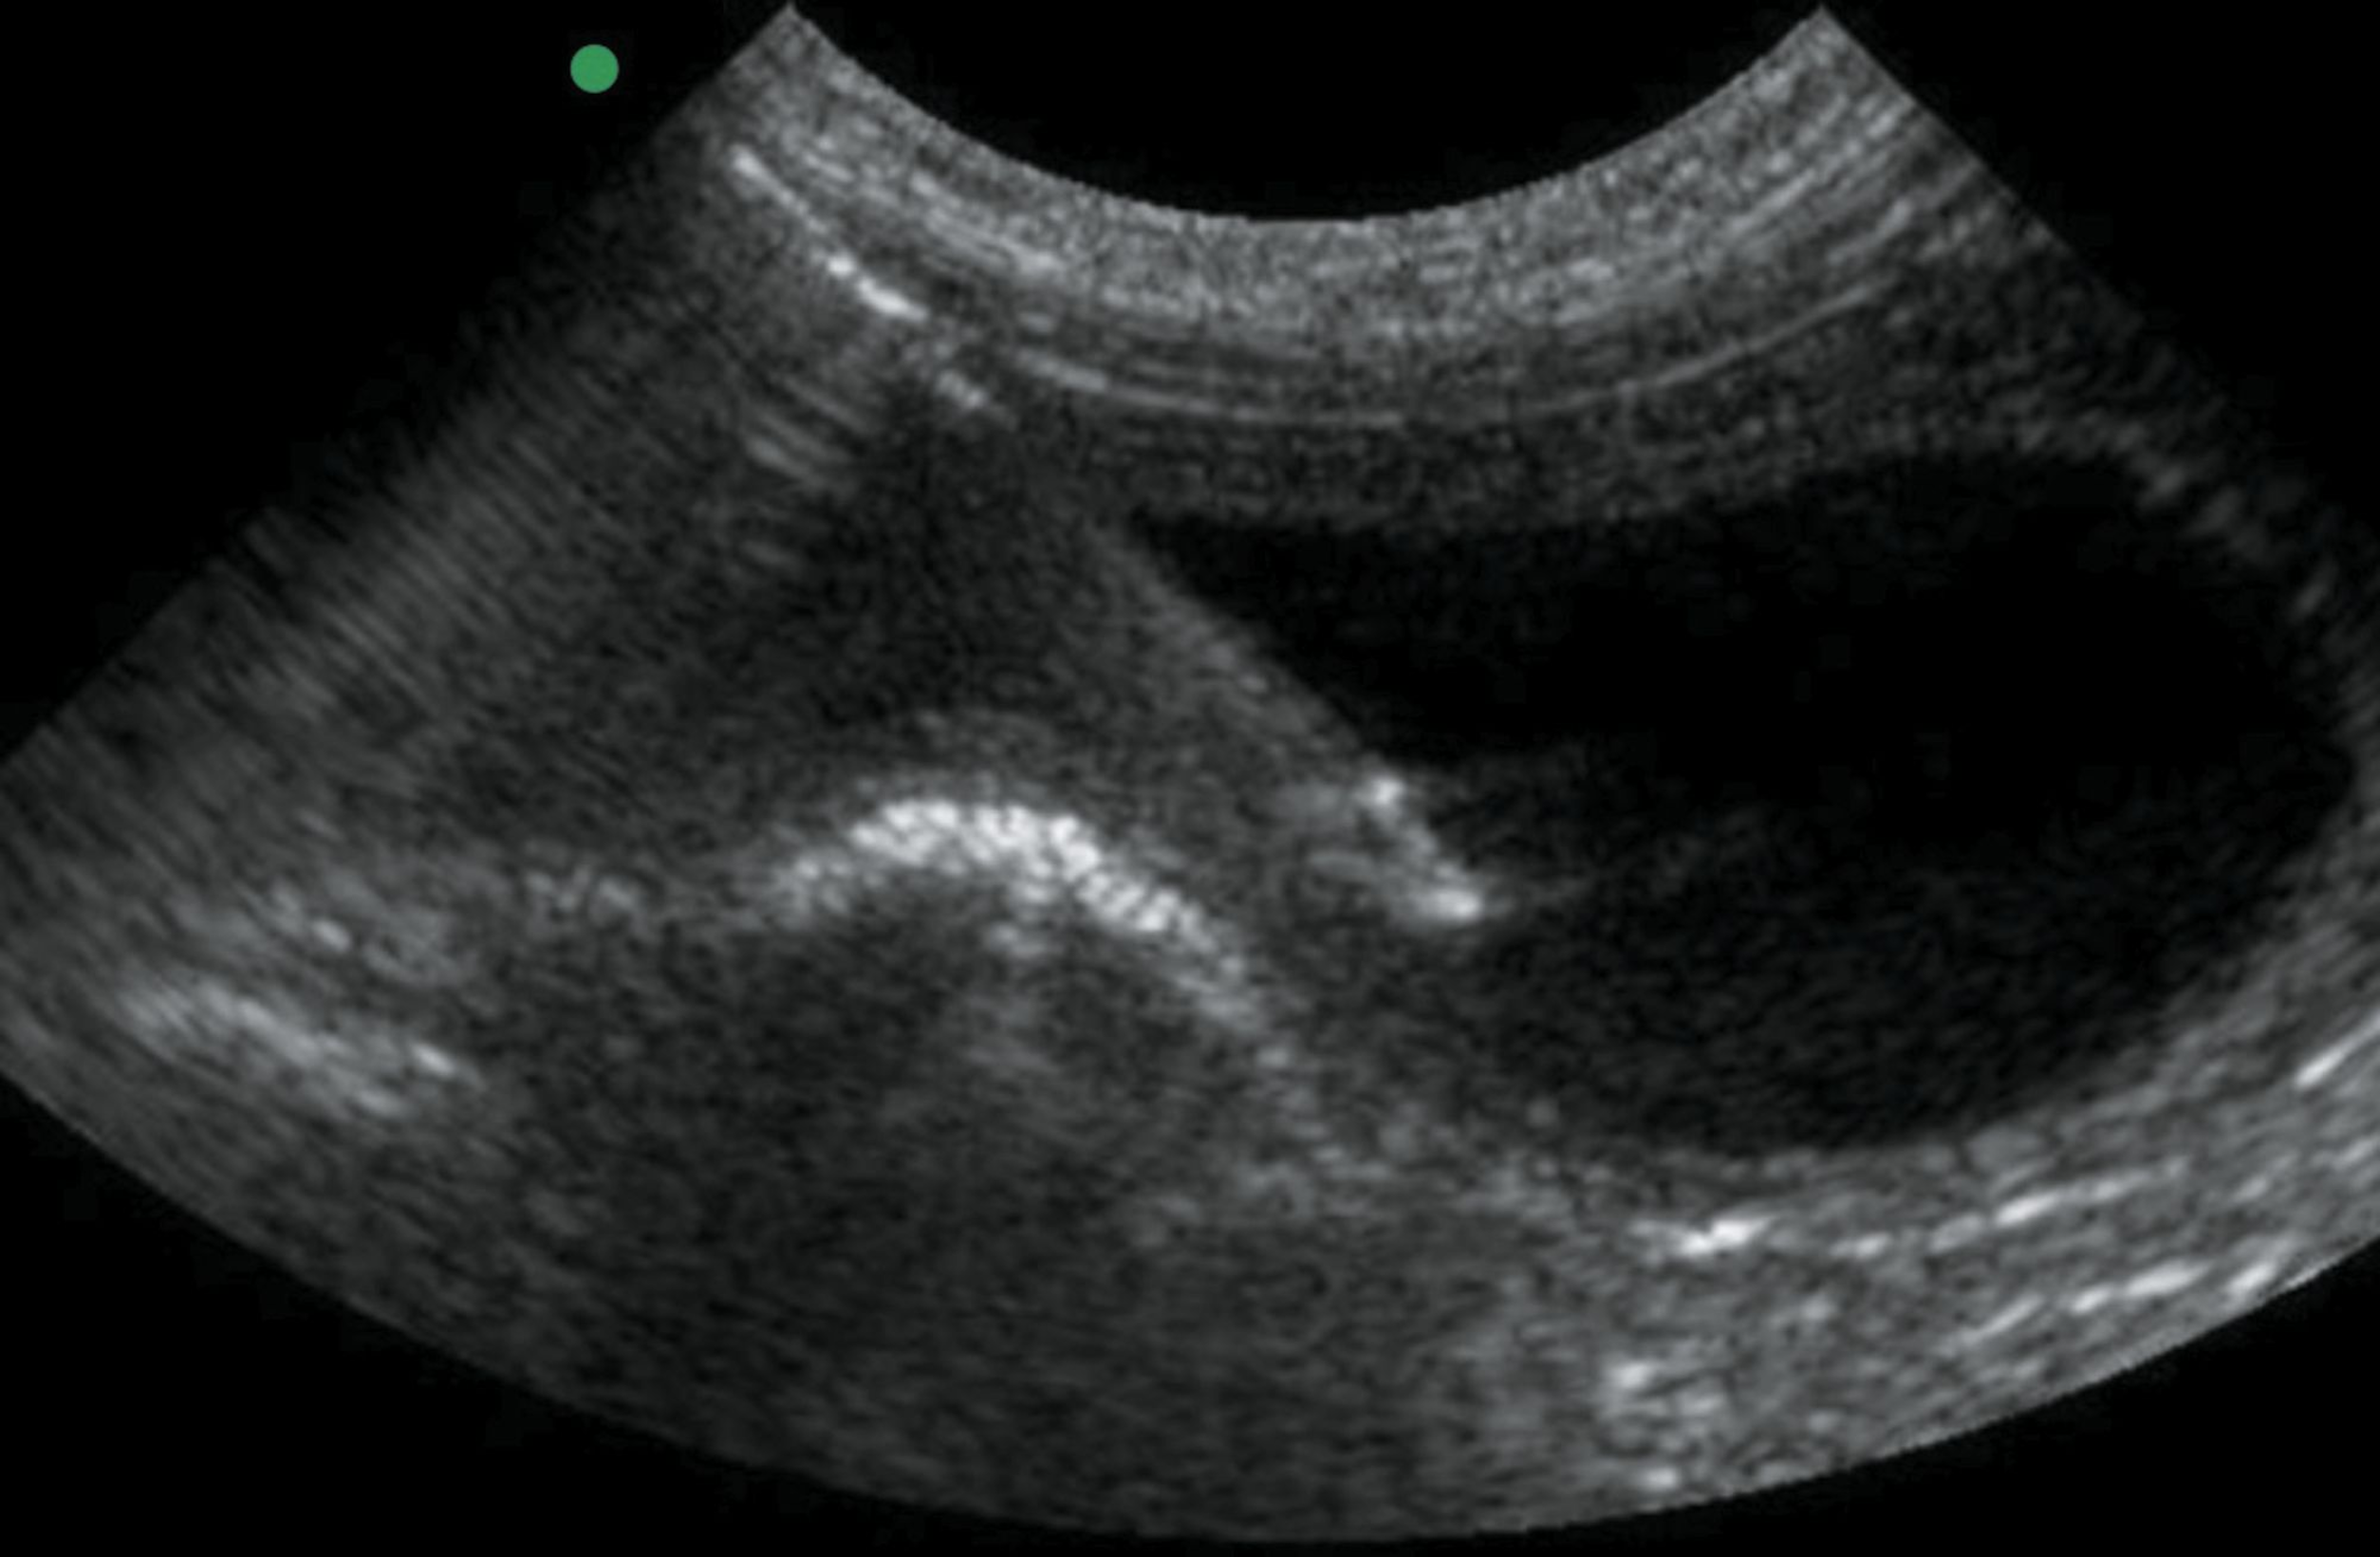

pleural effusion cat ultrasound

A thoracic chest ultrasound can also help. Pleural effusion cat has lung cancer.

Caudal is to the left of the image. Four criteria have been described to differentiate ascites from pleural. My cat is a female 8 years old no specified pedigree but its closer to a siamese cat weights around 4kilos now i believe due to the lost weight 5kg.

The chest wall may seem incompressible in cats with thoracic effusion. Cats with pleural effusion often have rapid shallow breathing. Of the cats that received thoracic ultrasound most exhibited bilateral pleural effusion 93.